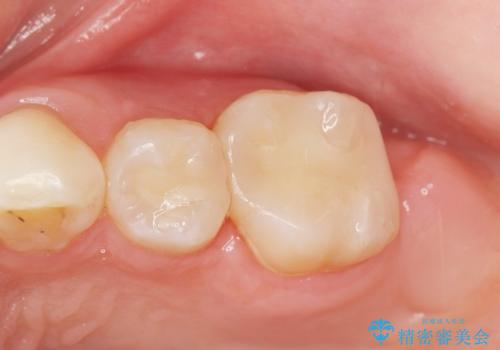

う蝕を丁寧に除去したのち、セラミックインレーによる修復を行いました。

セラミックインレーの審美的な仕上がりと自然な咬み心地にご満足頂けました。

「フロスを通したときの嫌な臭いもなくなった」と喜んで下さいました。

インレーの種類:セラミックインレー(e-max press)